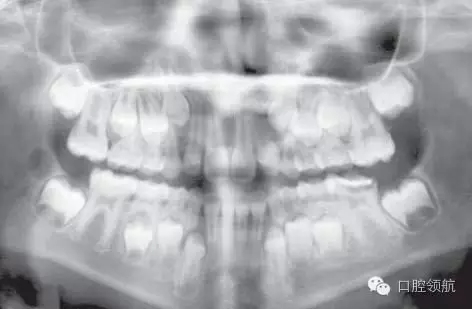

這是一個(gè)全科牙醫(yī)轉(zhuǎn)診的病例。該名女性患者I類錯(cuò)牙合,輕度擁擠,LL6嚴(yán)重齲壞,無(wú)法保留。患牙有間歇性的夜間痛,使其在夜間痛醒。圖2.8是由全科牙醫(yī)提供的最近的全景片。

圖2.8

全景片上最主要的特征有哪些?

● 混合牙列。

● 切牙已萌出。

● LL6嚴(yán)重齲壞;可見(jiàn)遠(yuǎn)中根根周感染,有臨時(shí)修復(fù)體存在。

● 除第三磨牙以外所有恒牙都存在(LR8可見(jiàn)早期牙胚發(fā)育)。

● 第二磨牙的牙冠發(fā)育完成。下頜的根間區(qū)域已開(kāi)始發(fā)育。